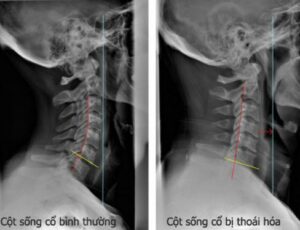

Đau mỏi vai gáy là tình trạng khá phổ biến hay gặp ở người cao tuổi, người hay khuân vác nặng, công việc thường xuyên phải cúi xuống, nằm sai tư thế…làm ảnh hưởng đến cấu tạo, hình dạng của đốt sống.

Là biểu hiện của thoái hóa đốt sống cổ, gai đốt sống, thoát vị đĩa đệm, xẹp hay biến dạng đĩa đệm…làm cho vùng vai gáy bị đau, co cứng cơ, đau tê có thể lan xuống vai, cánh tay và lưng trên.